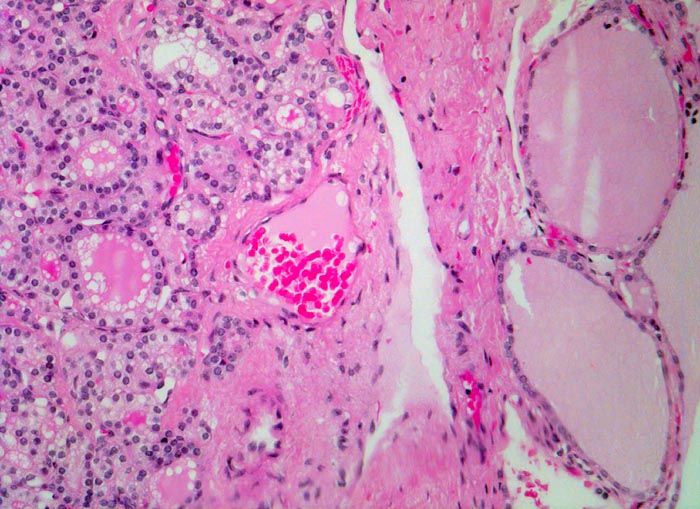

Das Gewebe des Adenoms (links) ist verschieden vom Gewebe der angrenzenden Schilddrüse (rechts), aber mühelos als Schilddrüsengewebe identifizierbar. Der Knoten ist von einer Kapsel umgeben und dadurch scharf von der Umgebung abgegrenzt. Die Follikel im Adenom sind deutlich kleiner. Die Lumina sind klein oder gar nicht nachweisbar. Das Kolloid weist zahlreiche Resorptionsvakuolen auf. Das übrige Schilddrüsenparenchym ist makrofollikulär. Die Follikel sind mit Kolloid gefüllt. Resorptionsvakuolen sind nicht erkennbar. Das Epithel ist abgeflacht.

Die 52-jährige Patientin gibt an, in letzter Zeit vermehrt Herzpalpitationen verspürt zu haben. Zusätzlich sei ihr aufgefallen, dass sie nervöser geworden sei, teilweise sogar aggressiv. Sie stellte eine ungewollte Gewichtsabnahme fest.

In der insgesamt eher verkleinerten Schilddrüse ist ein solitärer nicht schmerzhafter Knoten palpabel. Sonographisch kann der klinische Befund bestätigt werden. Die Szintigraphie ergibt eine vermehrte Speicherung von 123-Iodid im Knoten. Freise T3 und T4 sind erhöht, das TSH ist erniedrigt.